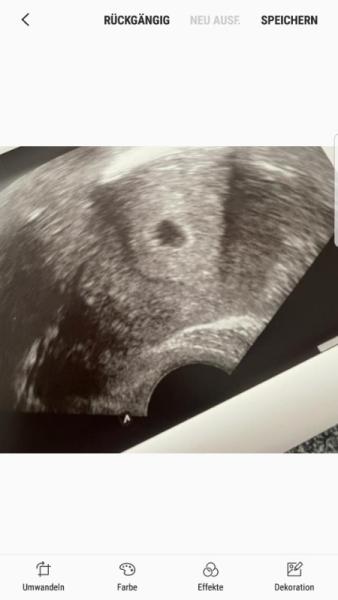

Hey liebes, das ist ja wirklich eine blöde Situation und ich kann es gut nachvollziehen das du dich einfach scheise fühlst. Die Test schauen echt positiv aus aber warum da solche Schwankungen sind kann ich mir auch nicht erklären ich glaube da bleibt wirklich nur abwarten auch wenn die warterei immer blöd ist.. Wenn man in der 6ssw nichts sehen konnte und der Hcg so niedrig ist würde ich mir persönlich keine Hoffnungen machen da man dort eigentlich was sehen sollte kann mal mein Ultraschall anhängen das müsste auch 5-6 ssw gewesen sein.. Ich hoffe das Glück ist ganz bald auf deiner Seite drück dir die Daumen!

Bild zu